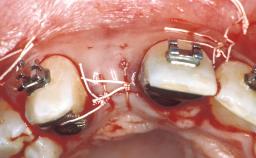

Replacement of an Upper Right Central Incisor with a Regular Neck Implant, Restored with an All-Ceramic Crown, Cemented

The 54-year-old male patient, a non-smoker, had ceramometal crowns on teeth 11 and 12 that no longer met his esthetic needs. The patient was free of pain. His medical history was without significant findings, and the patient was in good general health. The patient’s wish was to improve the esthetics of his anterior teeth. At full smile, the patient presented a medium to high lip line, displaying the full crowns and the marginal gingiva. The harmony of the gingival margin was disrupted by the now rejected ceramo-metal crowns on teeth 11 and 12. The crowns differed from the respective contralateral teeth in shape, texture, and color. The patient’s gingival biotype was thick, with a broad band of attached keratinized gingiva and a moderate (medium) scallop height. The soft tissues were free of recessions. The patient’s soft-tissue situation was favorable due to the slight soft-tissue excess at the buccal gingival margin of tooth 11 compared to that of tooth 21.